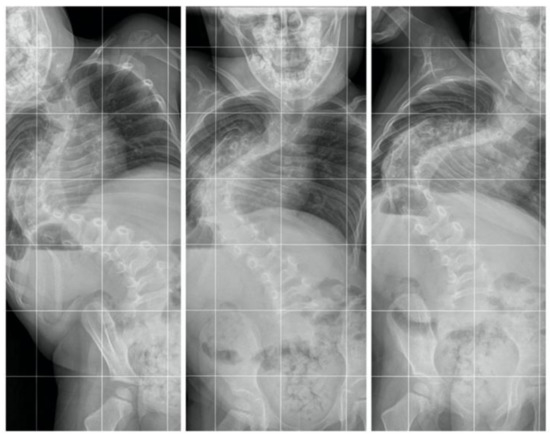

A 2-year-old girl was admitted to our clinic with rapidly progressive thoracic scoliosis. Previously, the patient had undergone conservative treatment with a brace and physical therapy. The patient had no other disorders. The major curve of the thoracic spine Cobb angle was 70° at 16 months of age, 100° at 22 months, and 122° at 30 months (Figure 1).

Figure 1.

Showed standing: (from left to right) AP X-rays at 16 months old (70 degrees), 22 months old (100 degrees), and 30 months old (122 degrees).